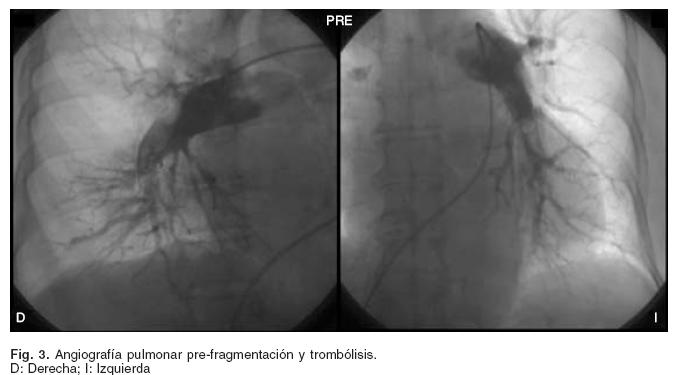

Se le realizó cateterismo derecho y angiografía pulmonar encontrándose la presión auricular derecha (PAD) 11 mmHg, D2VD 27 mmHg, PS AP 83 mmHg, presión media de la arteria pulmonar (PMAP) 42 mmHg. Rama derecha de la arteria pulmonar con imagen de trombo con oclusión completa de la arteria del lóbulo medio, con múltiples defectos sub–segmentarios del lóbulo inferior; arteria pulmonar izquierda (API) con oclusión completa de la arteria a nivel de la língula y múltiples defectos de llenado en la rama del lóbulo inferior (Fig. 3); se realizó fragmentación y trombólisis in situ con 50 mg de activador tisular del plasminógeno recombinante (rt–PA). La presión arterial sistémica al inicio del procedimiento fue 85/50 mmHg, posterior a la fragmentación–fibrinólisis 100/70 mmHg, y seis horas después 110/70 mmHg sin apoyo de fármacos presores.